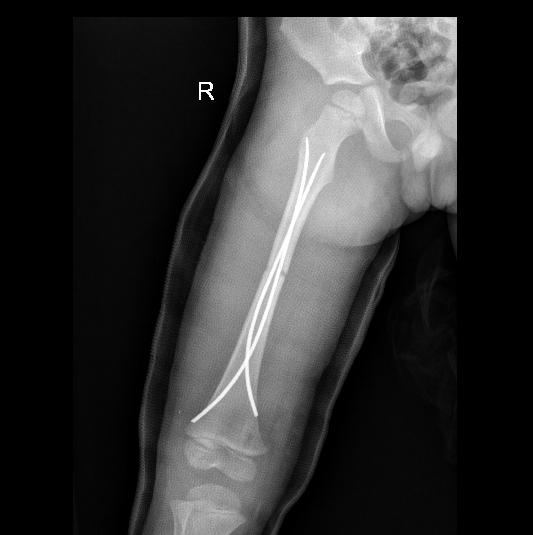

我科采用弹性髓内钉技术治疗儿童四肢骨干稳定性骨折,相比传统手术技术,切口小,创伤小,不影响骨骺生长板,不给生长带来麻烦。